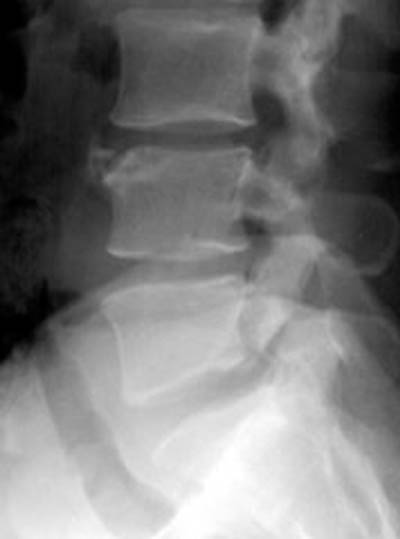

19) Name the abnormality shown in the image below.

20) In which demographic is the injury shown above most common?

21) At which spinal level is the injury shown above most common?